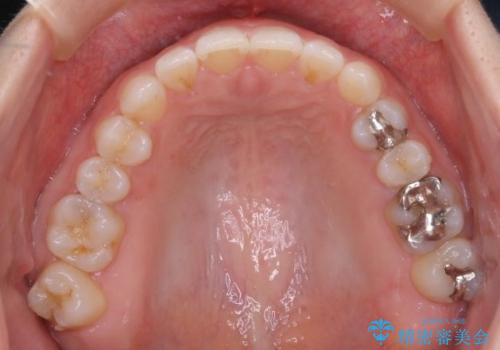

- 前歯の正中離開(すきっ歯)の改善を希望され来院された患者様です。

初診時の歯並びの状態としては、上顎中切歯間に1mm程の隙間があり、その他に見た目に関して気になるような問題点はない状態でした。

インビザライン(マウスピース)にて上顎のみの矯正治療を行いました。

見た目、嚙み合わせ及び、治療期間や施術内容に大変ご満足いただきました。